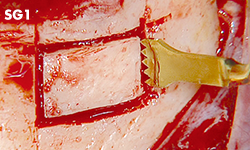

Nivelación de la cresta alveolar o escisión ósea.

Nivelación de la cresta alveolar o escisión ósea.

Nivelación de la cresta alveolar o escisión ósea.